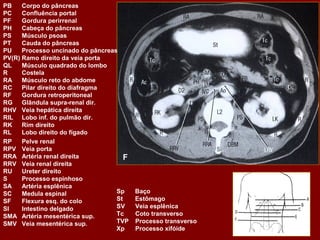

PB Corpo do pâncreas PC Confluência portal PF Gordura perirrenal PH Cabeça do pâncreas PS Músculo psoas PT Cauda do pâncreas PU Processo uncinado do pâncreas PV(R) Ramo direito da veia porta QL Músculo quadrado do lombo R Costela RA Músculo reto do abdome RC Pilar direito do diafragma RF Gordura retroperitoneal RG Glândula supra-renal dir. RHV Veia hepática direita RIL Lobo inf. do pulmão dir. RK Rim direito RL Lobo direito do fígado RP Pelve renal RPV Veia porta RRA Artéria renal direita F RRV Veia renal direita RU Ureter direito S Processo espinhoso SA Artéria esplênica SC Medula espinal Sp Baço SF Flexura esq. do colo St Estômago SI Intestino delgado SV Veia esplênica SMA Artéria mesentérica sup. Tc Coto transverso SMV Veia mesentérica sup. TVP Processo transverso Xp Processo xifóide